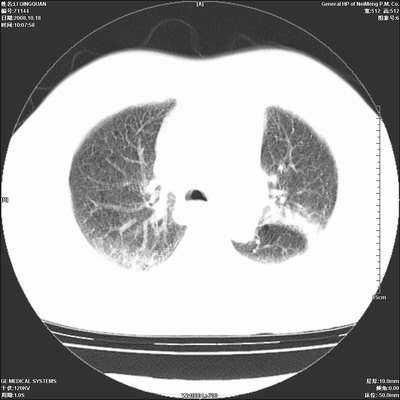

以下是引用ybing在2008-10-19 12:58:00的发言:[br]左肺上叶阻塞性炎症-建议支气管镜进一步检查除外中央型肺癌

以下是引用duguo在2008-10-19 13:59:00的发言:[br]左肺上叶支气管狭窄,首先考虑中心型肺癌伴阻塞性肺炎\\肺不张.

以下是引用随光逐影在2008-10-19 14:31:00的发言:[br]考虑左肺中央型肺癌并左肺上叶阻塞性肺炎,肺不张。